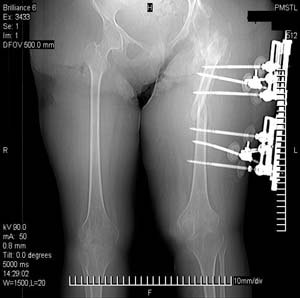

Пациентка 17 лет. В 5-летнем возрасте получила кататравму - осложнённый перелом позвоночника с повреждением спинного мозга в грудном отделе, нижняя параплегия с нарушением функции тазовых органов. Поступила к нам в отделение в сентябре 2007 по поводу патологического перелома левого бедра на фоне хронического остеомиелита бедра. Лечение стержневым аппаратом АВФ, достигнута консолидация. За время лечения развились массивные пролежни крестца и правого бедра с переходом в остеомиелит в/3 правого бедра, сепсис. Выполнено вскрытие гнойника, некрэктомия. Рана велась открыто. В дальнейшем - повторные некрэктомии, дермотензия.

>Можно наложить простейший аппарат таз-бедро и подвесить больного

Такая мысль тоже приходила. Не решились, так как:1.Выраженный остеопороз костей таза и бедра, больная тучная - высок риск того, что стержни не выдержат. 2.Сейчас больная передвигается в инвалидном кресле - хоть какая-никакая, а динамизация. Если лишить её этой возможности - застойная пневмония со всеми вытекающими...